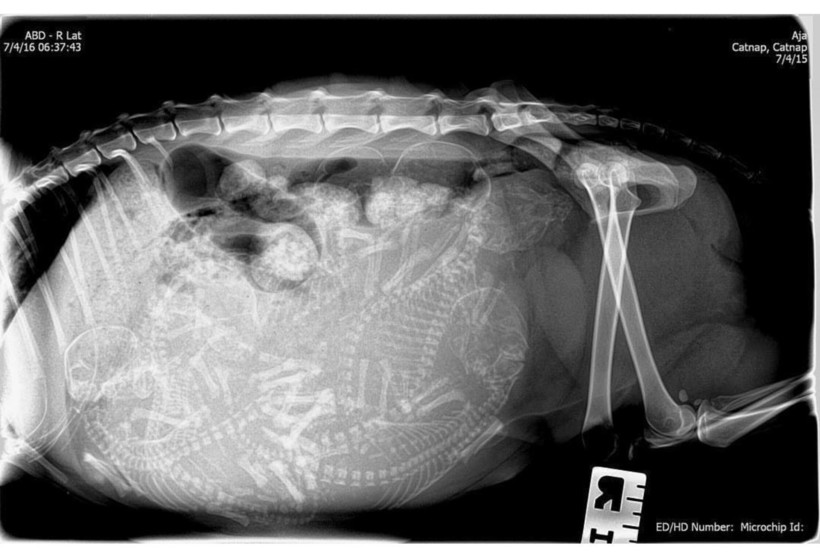

Собака и ее многочисленное будущее потомство